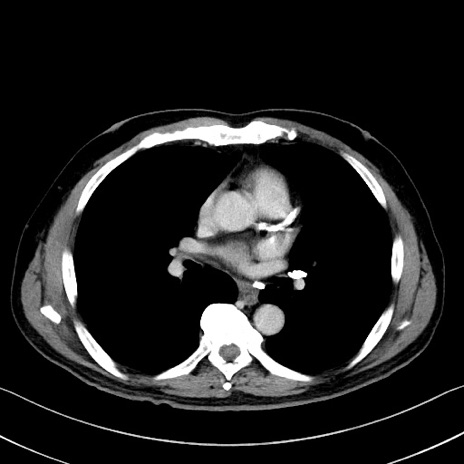

症例35(横断像)

【症例】70歳代 男性

【主訴】腹部膨満、嘔吐

【現病歴】昨日より腹部膨満感出現。本日増悪し、仙痛出現。嘔吐あり、受診。

【既往歴】糖尿病、胆摘後

【身体所見】BP 149/80mmHg、HR 74/min、BT 35.9℃、腹部:膨満、軟、圧痛なし。腸雑音減弱あり。上腹部正中切開瘢痕あり。

【データ】WBC 13500、CRP 1.72